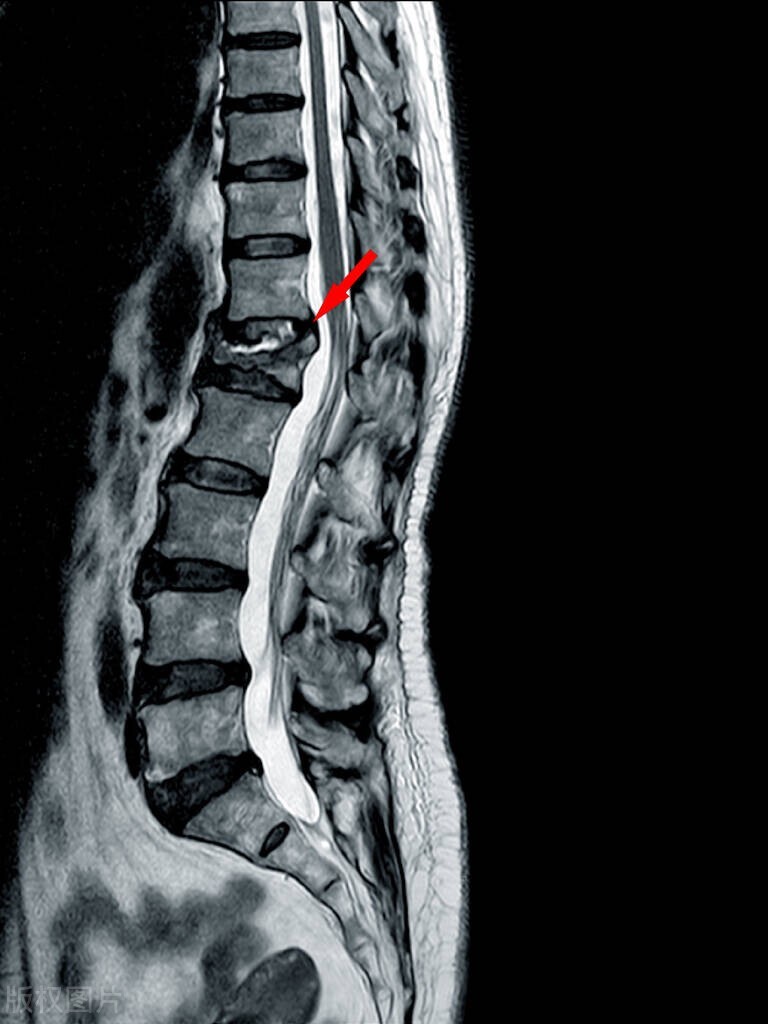

椎管狭窄综合征主要病理机制是肾虚不固,经络不通,气滞血瘀,营卫不和。

中医学认为椎管狭窄症分为肾精不足型、风寒湿阻型、气虚血瘀型三种,治疗多以补肾益精、祛风除湿、温经通络、益气养血、活血化瘀为主。